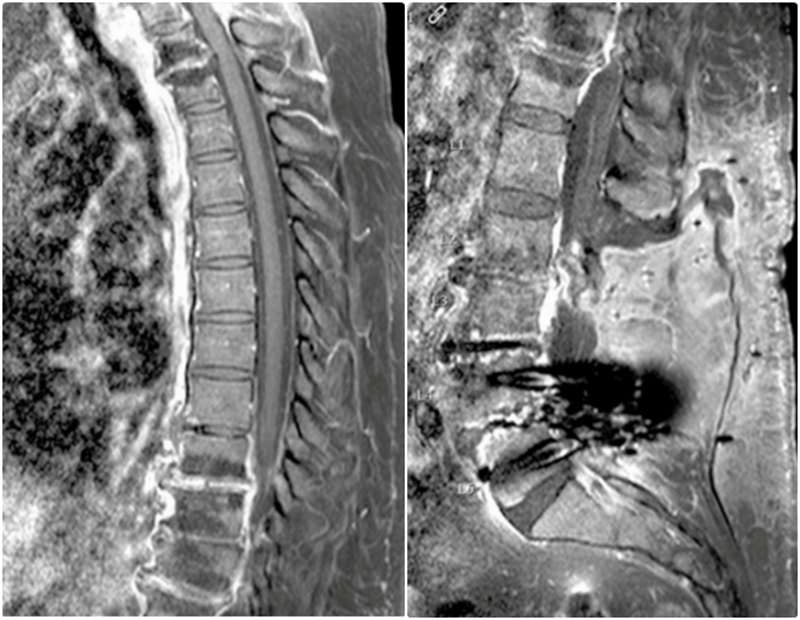

胸椎(A)和腰椎(B)脊柱MR图像显示C7-T1以及T1-2和T9-12椎间盘内有一些强化。从T9到T12也有腹侧硬膜外强化

腰椎MRI,L2和L3椎体强化,骨髓水肿,伴椎前/椎旁软组织肿胀,弥漫性椎间盘膨出,黄韧带增厚,椎管狭窄

腰椎MRI,L2/3明显狭窄,左侧明显,伴椎间盘炎和中度硬膜囊压迫,周围可见软组织水肿,左侧腰大肌轻度水肿。